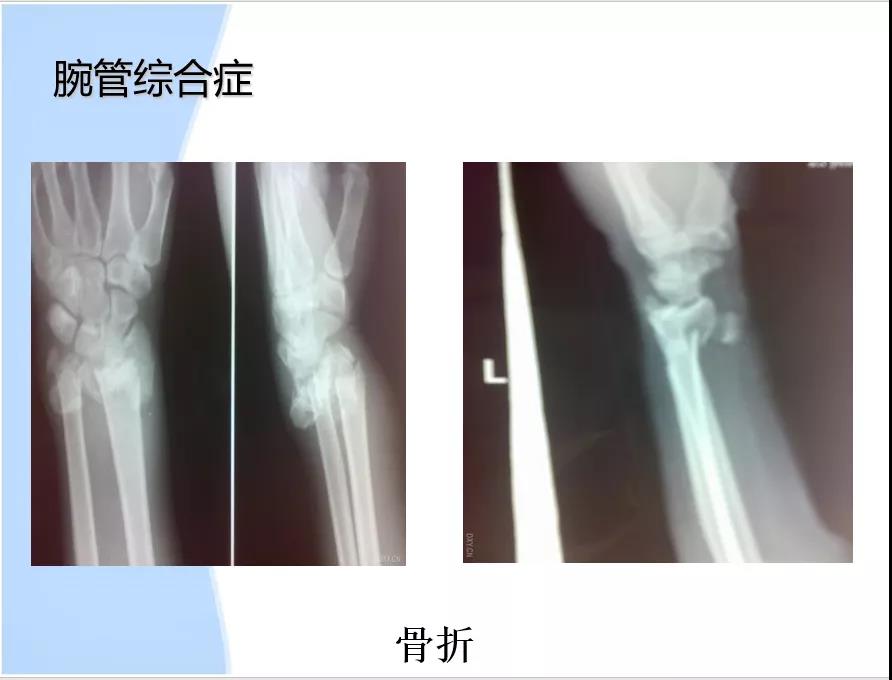

腕管综合征

由于正中神经在腕管内受压而造成大鱼际肌无力和正中神经支配区的疼痛、麻木及进行性鱼际肌萎缩。又称迟发性正中神经麻痹

病因:1、腕管容量减小:月骨前脱位,腕部骨折(colles 反colles smith);腕和腕间关节增生性关节炎;腕横韧带增厚;感染或外伤致软组织水肿。2、腕管内容物增加:肿瘤(脂肪瘤、黄色瘤);腱鞘囊肿;腱鞘滑膜炎;3、解剖异常。4、正中动脉压迫。5、腕管内出血:外伤或血友病引发腕管内出血。6、其他:绝经;妊娠;痛风;类风湿;甲状腺功能低下。

诊断1 临床表现。2 Tinel征阳性。3 Phalen征阳性。4 X-ray鉴别骨折、脱位及增生。